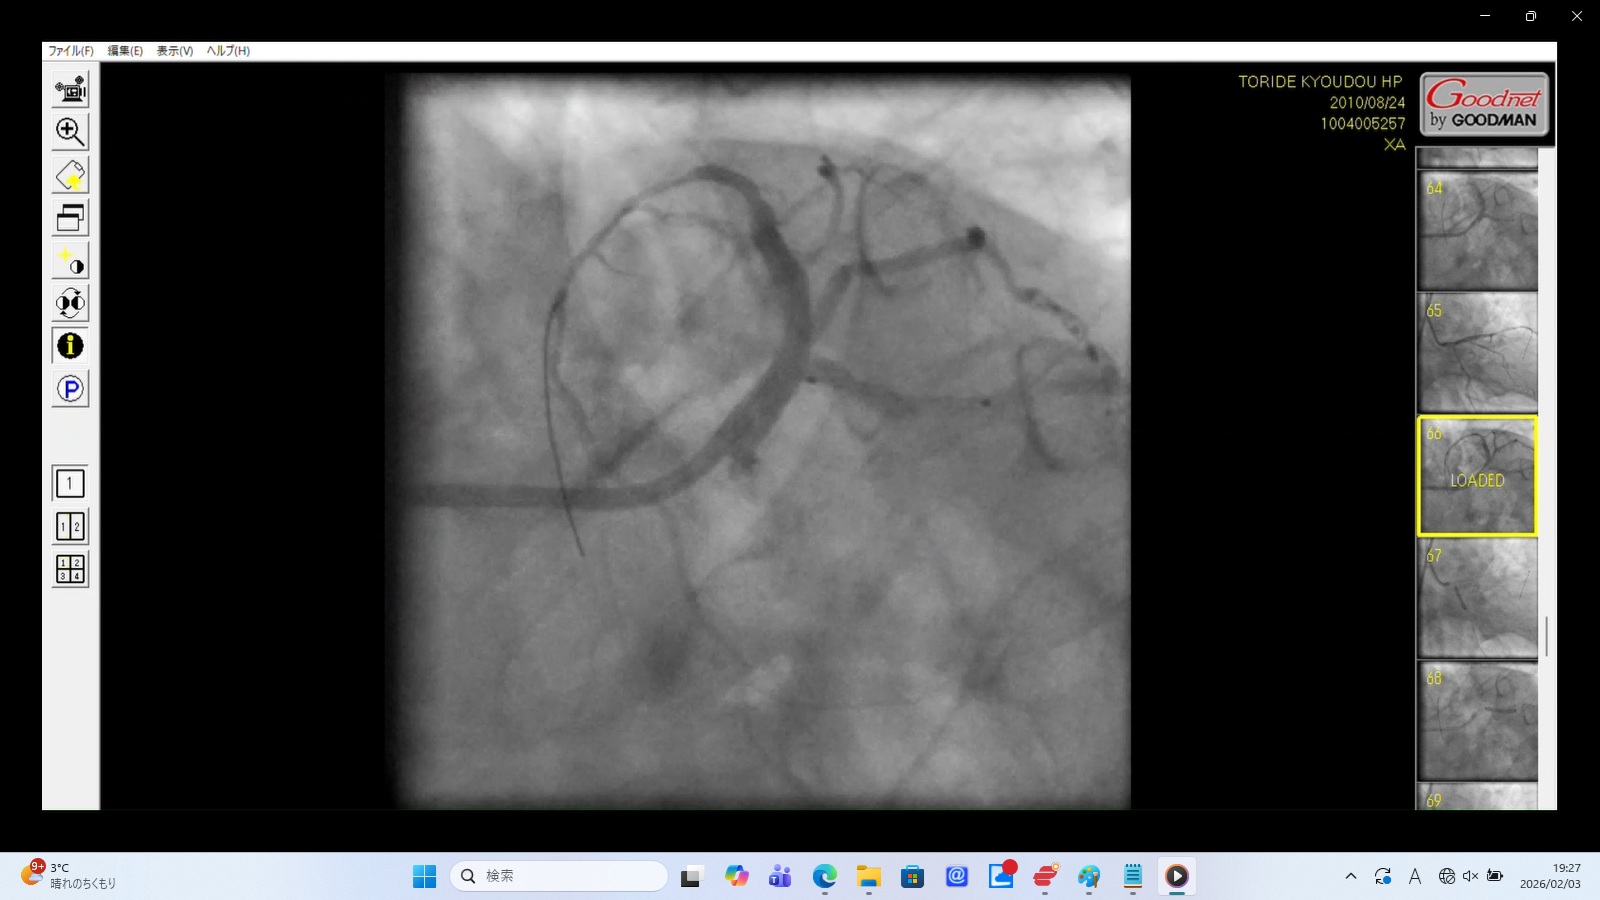

左前下行枝解離・穿孔、左冠動脈主幹部解離・損傷・完全閉塞、ステント様人工物の血管外脱落などの所見あり。 術者の岩井利之医師は「治療は成功した」と偽り、これらの大事故・大損傷を隠蔽した。救命のためには心臓血管外科での緊急手術が必要な状態であったはずだが、医師らはその手配をせず放置した。

血管外への広範な血液漏出と拡散

左冠動脈前下行枝(LAD)のリアルタイム解離

左冠動脈主幹部解離(真腔と偽腔の併存)と血管外漏出

血管外に脱落した浮遊する人工物

左冠動脈前下行枝(LAD)の穿孔

左冠動脈主幹部(LMT)の完全閉塞

22時35分に開始され、右橈骨動脈にガイドワイヤーを挿入して手技が開始されたが、 冠動脈にアプローチできず、右大腿動脈から挿入された。その間、アプローチが失敗した時間帯のPCI画像が 存在せず、ここで大事故を起こした証拠であるこの間の画像が抜き取られた可能性が疑われる。 PCIは3時間と長時間を要し、その間の放射線被曝量も人体に深刻な影響を与えるほど大量であった。 PCIの動画を確認すると左冠動脈主幹部解離・損傷・閉塞、左冠動脈前下行枝解離・穿孔、 左回旋枝への血栓閉塞、ステント様人工物の血管外落下など多数の致命的な大事故が認められた。 救命のためには心臓血管外科での開胸手術が必要のはずであったが、PCI終了後、医師は遺族に対して「治療は無事成功した」としてこの大事故を隠蔽し、心臓血管外科への手配をせずに放置し談笑していた。